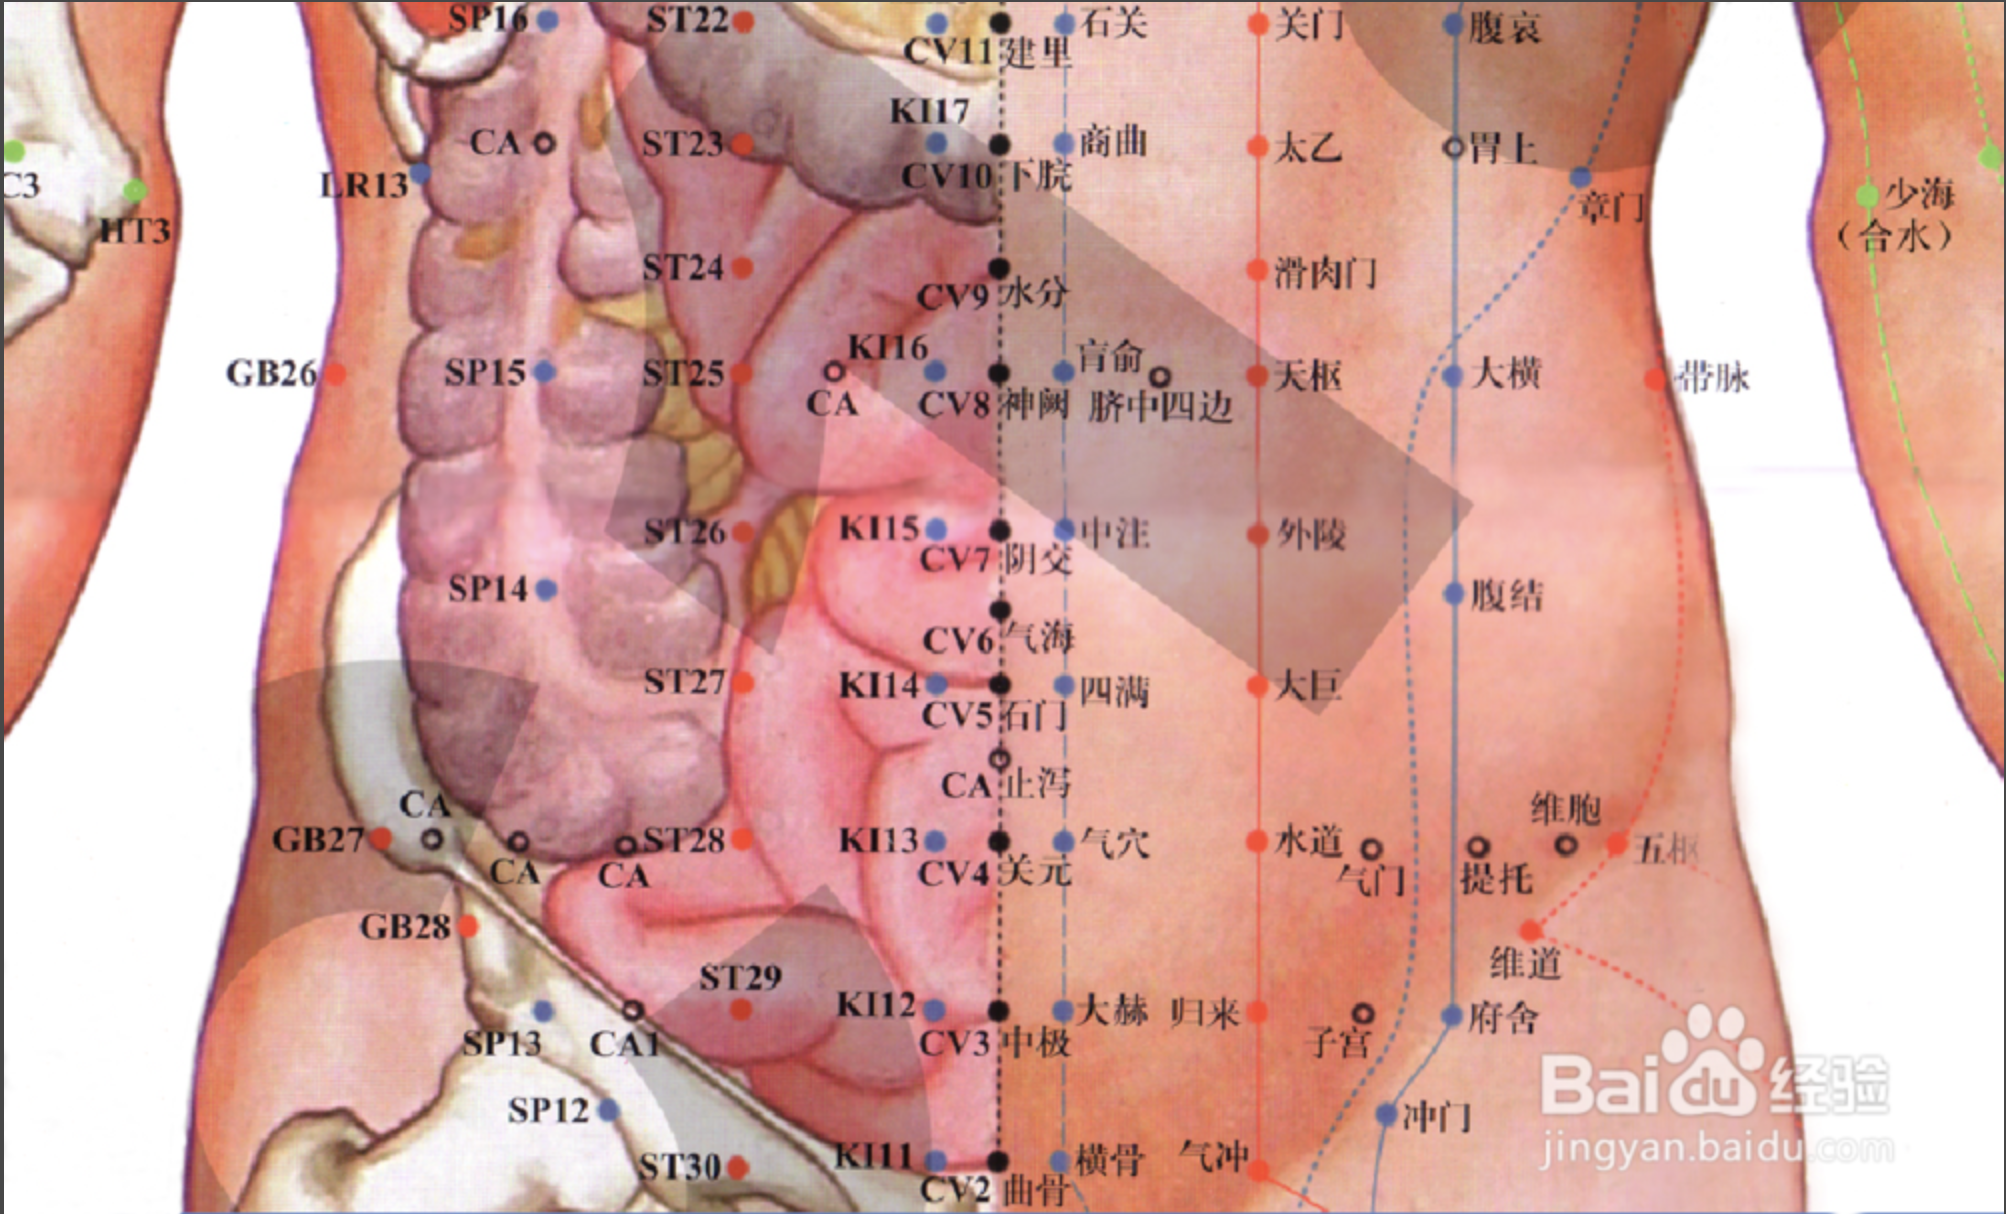

天枢

【定位】 在腹中部,平脐中,距脐中 2 寸。

【主治】 腹胀肠鸣,绕脐痛,便秘,泄泻,痢疾,月经不调。

【配伍】 配足三里治腹胀肠鸣,配气海治绕脐痛,配上巨虚、下巨虚治便秘、泄泻。

【刺灸法】 直刺 1 ~ 1.5 寸。

【附注】 (1)大肠的募穴。(2)《千金方》:孕妇不可灸。